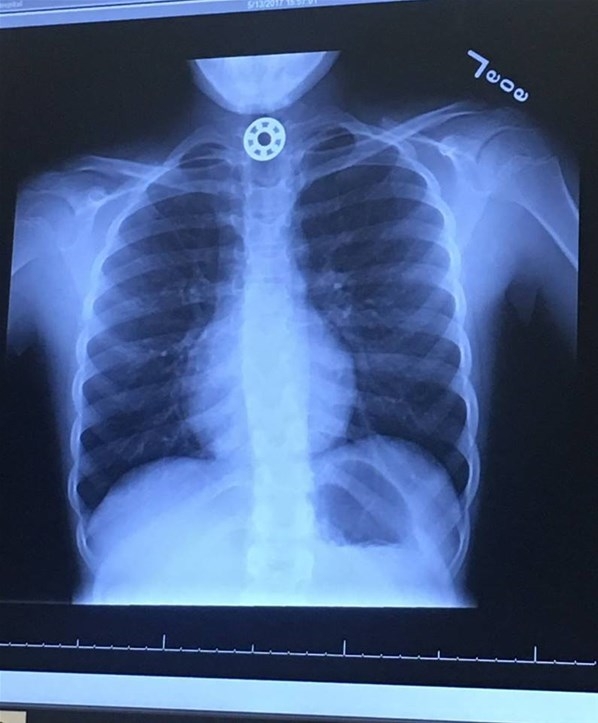

ABD'nin Houston kentinden bir kadın, kızının boğazına kaçan demir para büyüklüğündeki stres çarkının bir parçasını çıkarmak için ameliyat edilmek zorunda kalmasının ardından Facebook hesabından anne babaları uyardı.

Houston'ın hemen kuzeyinde, The Woodlands'daki Texas Çocuk Hastanesine götürülen çocuğun yutağında bilye büyüklüğünde bir şeyin sıkıştığı görüldü ve hemen ameliyat yapılması gerektiği söylendi.